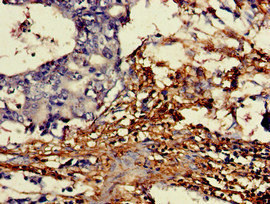

Immunohistochemistry of paraffin-embedded human gastric cancer using CSB-PA006593LA01HU at dilution of 1:100